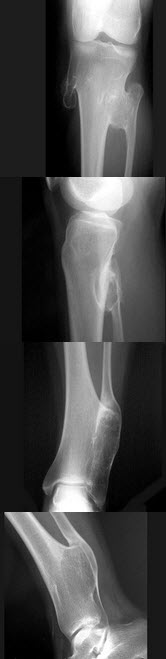

41、单项选择题

男,7岁,肘部外伤,根据所示图像,最可能的诊断是()

A.尺骨中上段骨折

B.桡骨小头脱位

C.孟氏骨折

D.盖氏骨折

E.以上均不正确

点击查看答案